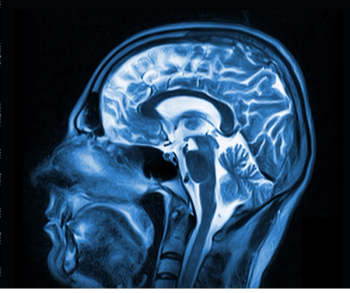

Radiotherapy for Prostate Cancer: Study Says MRI Guidance Significantly Reduces GU and GI Toxicities

For patients undergoing stereotactic body radiotherapy (SBRT) for prostate cancer, the acute genitourinary (GU) toxicity rate associated with the procedure was 19 percent lower with magnetic resonance imaging (MRI) guidance in comparison to computed tomography (CT) guidance, according to new research presented recently at the American Society for Radiation Oncology (ASTRO) Annual Meeting.